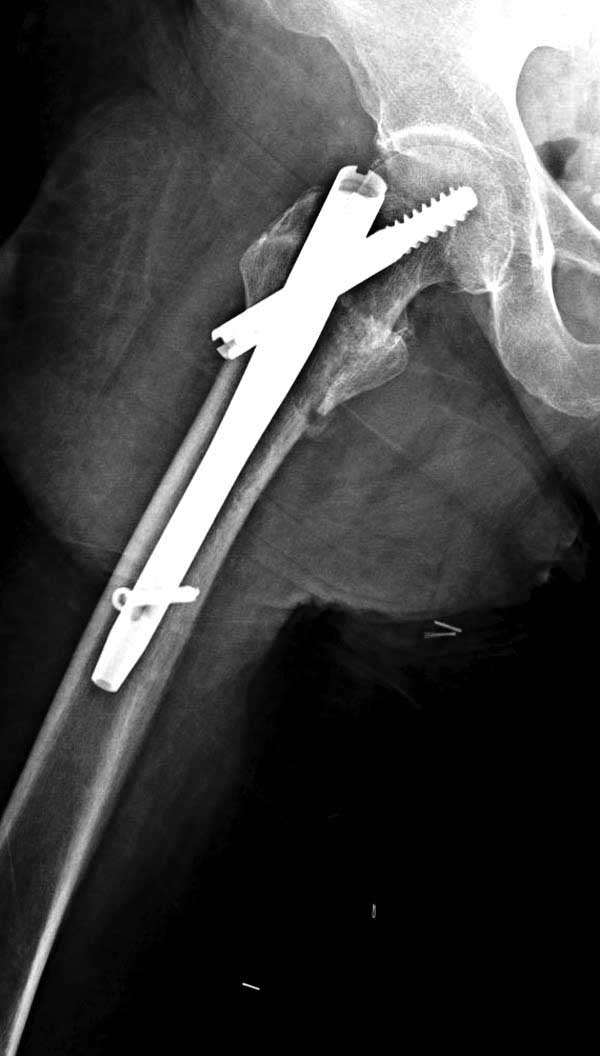

Повторно поступает после двух с половиной лет, где обнаруживается перелом на второй стороне. Немного сложно, но для фиксации выбрали Antegrade InterTan Smith Nephew Nail и с момента фиксации более 3х мес.

Имя     : 29 IT fx LT injury 0.jpg

Тип     : image/jpg

Размер  : 34633 байтов

Описание: отсутствует

Url     : http://weborto.net:8080/pipermail/ortho/attachments/20120509/52aada75/attachment-0050.jpg